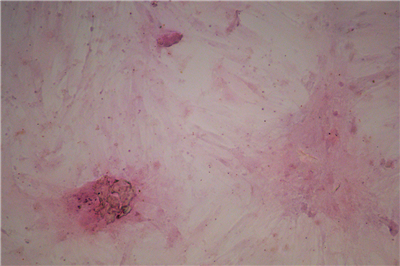

1.成骨诱导的过程是使钙离子能够以钙盐的方式沉淀下来,即“钙结节”,鉴定钙结节的染色方法常用茜素红染色法。

3.染色原理:茜素红与钙发生显色反应,产生一种深红色的带色化合物,这样成骨诱导的细胞外面沉积的钙结节也就被染成了深红色。.